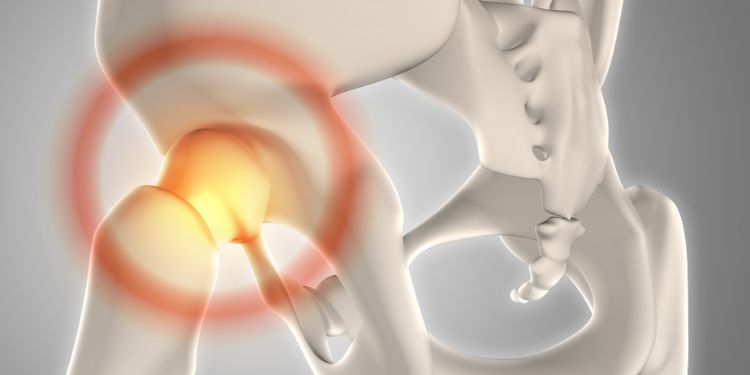

International Journal of Human Anatomy

ISSN :2577-2279

International Journal of Human Anatomy is a peer-reviewed journal dedicated to advancing the scientific knowledge of human anatomy and embryology.